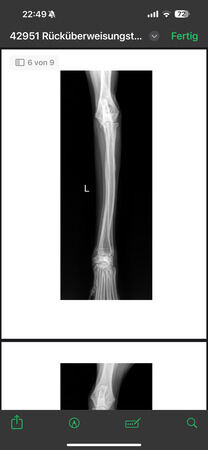

radiologisch kein Kniegelenkserguß oder Arthrose, nur Weichteilschwellung im Bereich distaler

Patellasehne, Elle proximal verdickt und Fehlstellung (alte, verheilte Fraktur?), keine deutlich

Ellbogenarthrose, leichtgradige Fehlstellung Unterarm li., auch leichtgradige Fehlstellung Radius re.

Alle Gelenke sonst ohne deutliche Arthrosezeichen.